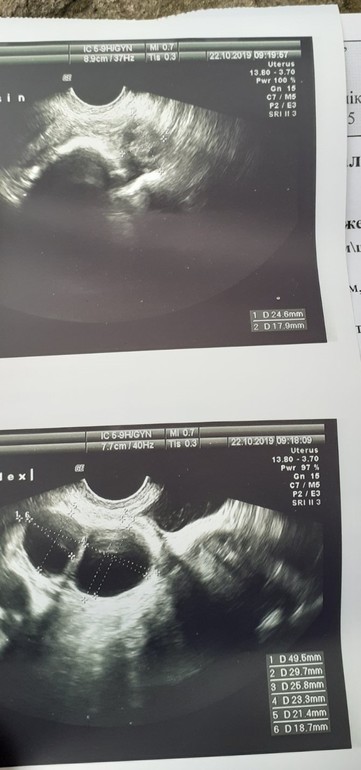

В этом цикле была стимуляция клостиком и у меня. Сейчас 4 ДПО, Овуляция была на 16 ДЦ из 28 в среднем. Своих овуляций за 28 лет можно на пальцах пересчитать, прогик стремился к нолю, а фолики не росли. Но со стимуляцией выросла аж два)))) я так рада! Это хороший препарат, ничего не бойтесь. Болело и у меня. Фолики очень большие растут на этом препарате, поэтому и боли. У меня аж в ноги отдавало, после овуляции попустит.. Вот УЗИ посмотрите, размеры нереальные просто, поэтому и боли) Крепитесь! Болят - значит растут!!! )))